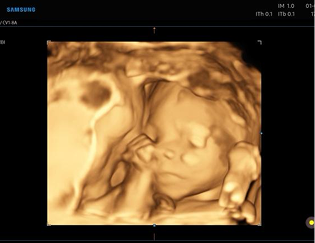

Licenciada en medicina por la Universidad Miguel Hernández de Elche (Alicante). Especialista en ginecología y obstetricia, vía MIR, por el Hospital General Universitario de Alicante. Especialista en diagnóstico prenatal y ecografía Doppler.